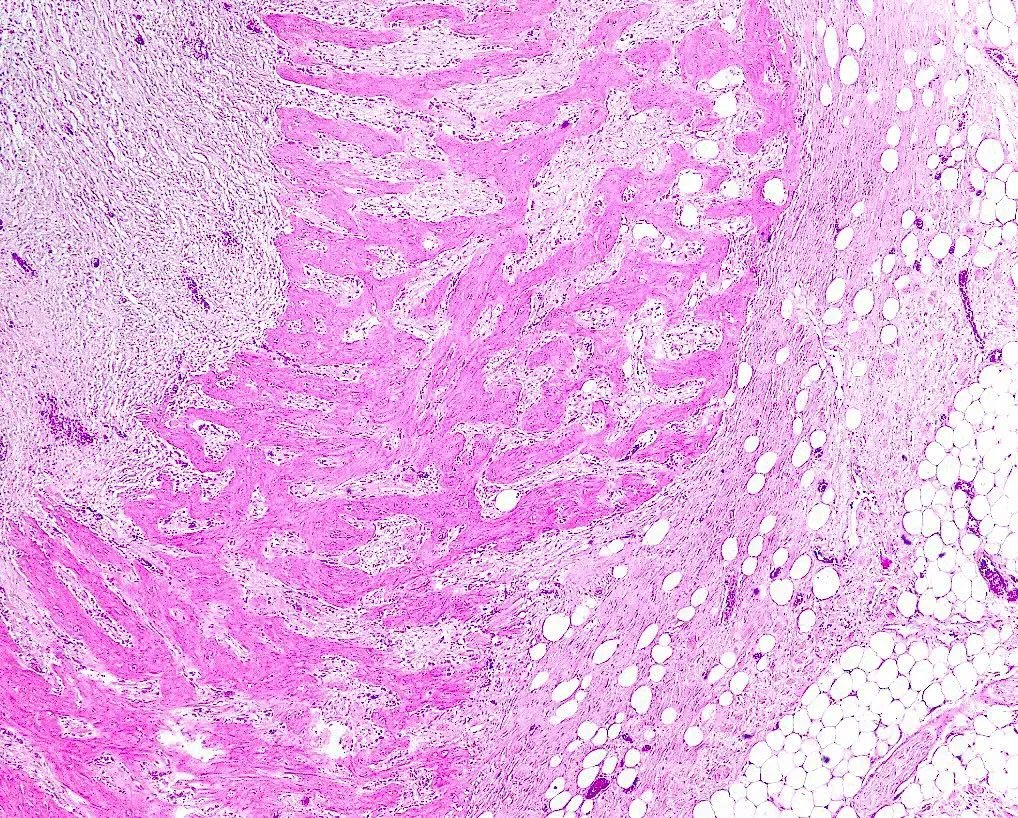

Thyroidectomy revealing eosinophilic tumor cells with tall morphology adjacent to normal thyroid tissue. What is the diagnosis? Answer: kikoxp.com/posts/12977 #PathArt #PathTwitter #MedTwitter